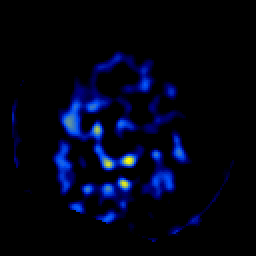

SPECT TL Study #6 -- Slice #48